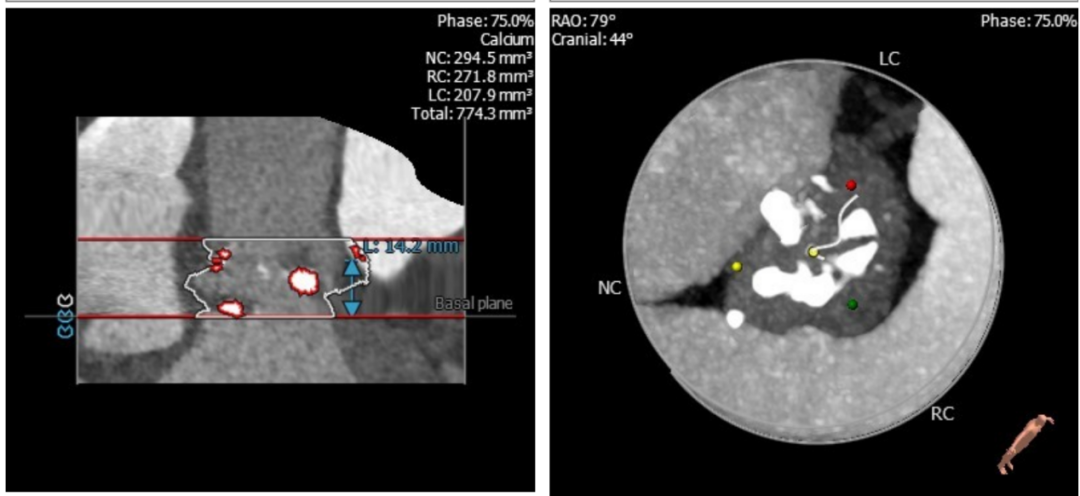

根部解剖:

这又是一个一波三折的病例,虽然最后病人顺利出院,不过当中确实非常曲折,手术策略也有很多值得商榷的地方,拿出来请大家批评指正。这个病人从超声看,是一个以反流为主的病例,狭窄只是中度,左室已经70。从CT分析看,瓣环-流出道呈开放性,左右冠瓣可疑融合,左冠高度虽然有14,但是左冠瓣叶很长,增厚,提示有冠脉风险。导丝刚跨瓣,病人就出现室颤,经药物调整后暂时稳定,25的球囊预扩后发现左冠完全不显影,而且患者再次反复室颤,此时为了稳定循环,第二因为冠脉风险,决定先从左侧股动静脉上ECMO保护。